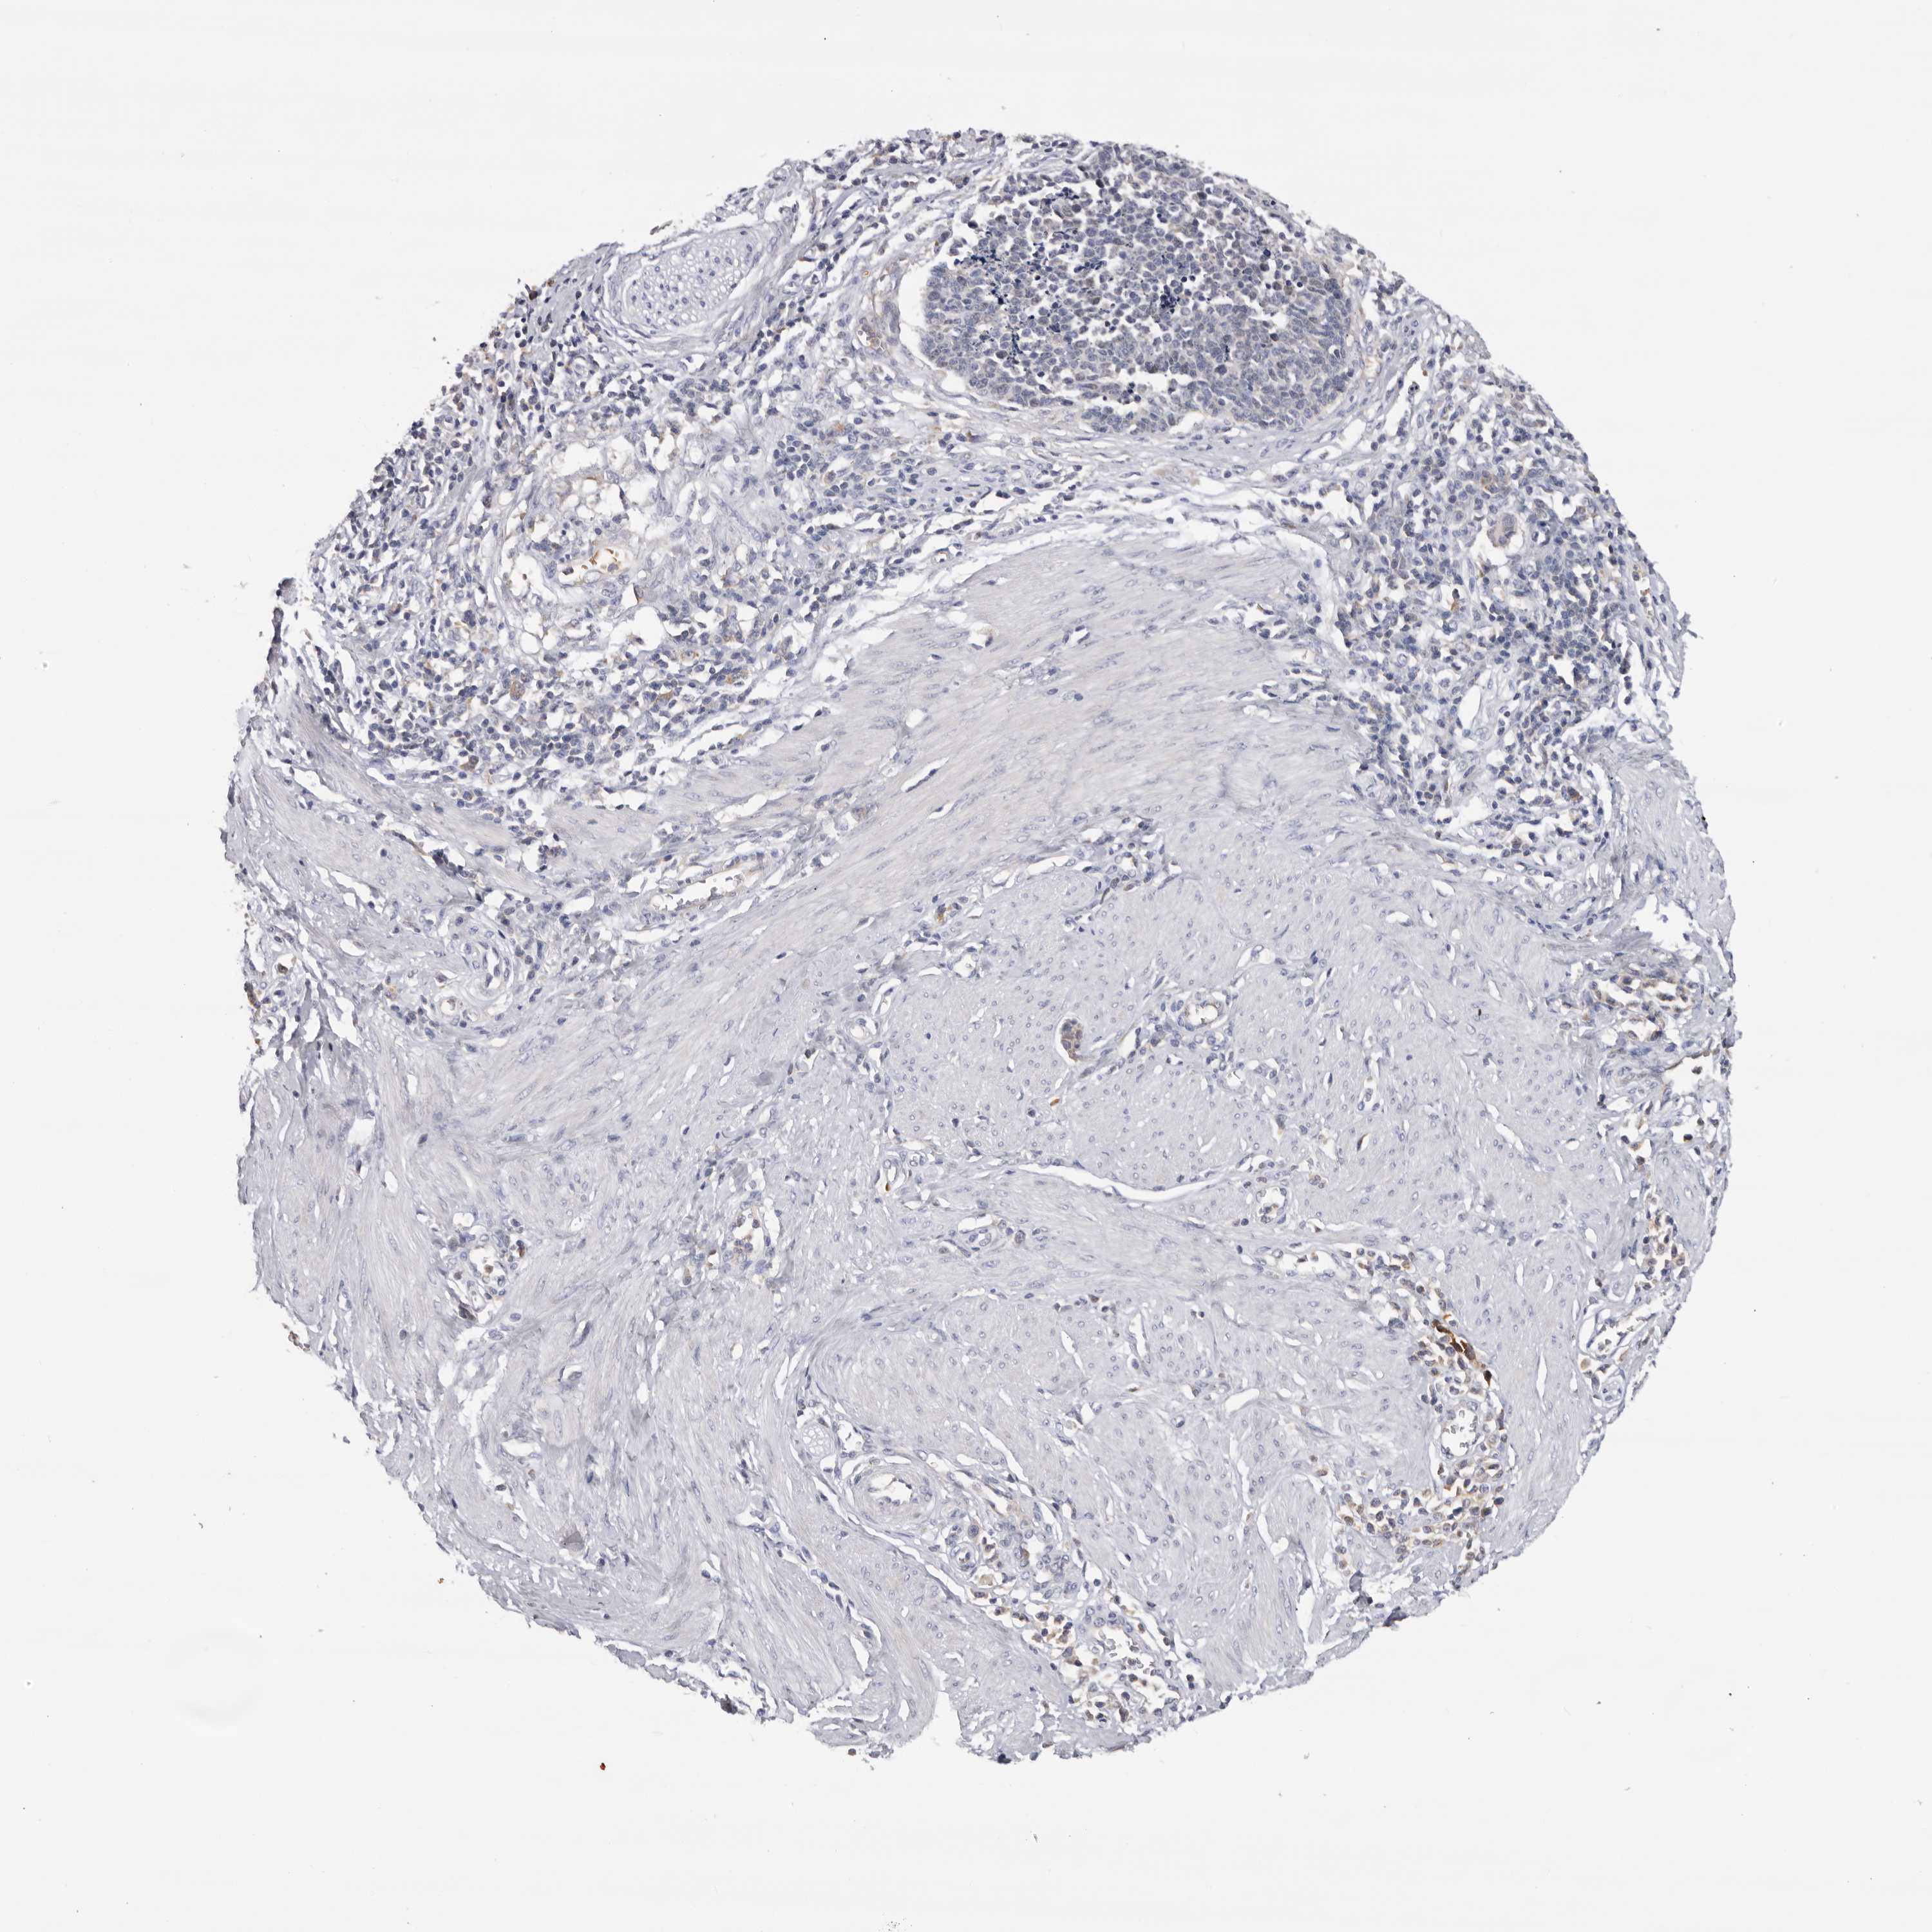

CERVICAL CANCER - Protein expressioni

A mouse-over function shows sample information and annotation data. Click on an image to view it in a full screen mode. Samples can be filtered based on level of antibody staining by selecting one or several of the following categories: high, medium, low and not detected. The assay and annotation is described here.

Note that samples used for immunohistochemistry by the Human Protein Atlas do not correspond to samples in the TCGA dataset.

Antibody stainingi

Antibody staining in the annotated cell types in the current human tissue is reported as not detected, low, medium, or high, based on conventional immunohistochemistry profiling in selected tissues. This score is based on the combination of the staining intensity and fraction of stained cells.

Each image is clickable and will lead to virtual microscopy that enables deeper exploration of all samples and also displays staining intensity scores, fraction scores and subcellular localization as well as patient and tissue information for each sample.

Antibody HPA023081

Antibody HPA023103

Antibody HPA024795

Squamous cell carcinoma, NOS

Adenocarcinoma, NOS